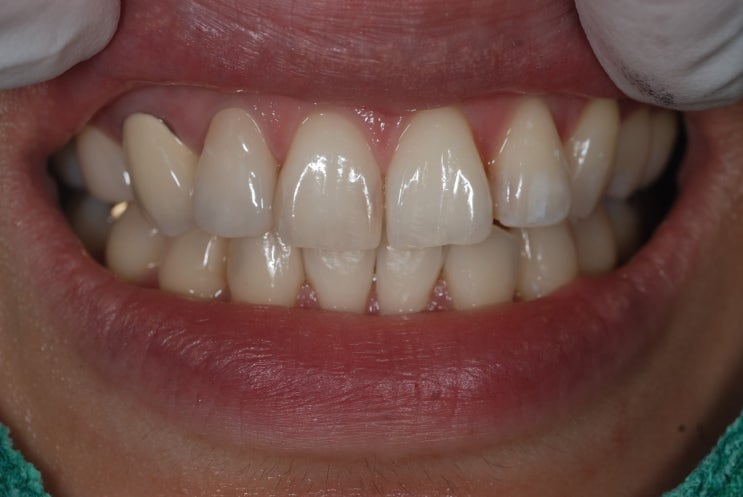

안녕하세요 수서역치과 문정도 치과 수서서울삼성치과 원장 이재현입니다 오늘은 신경치료 후 회복한 환자...